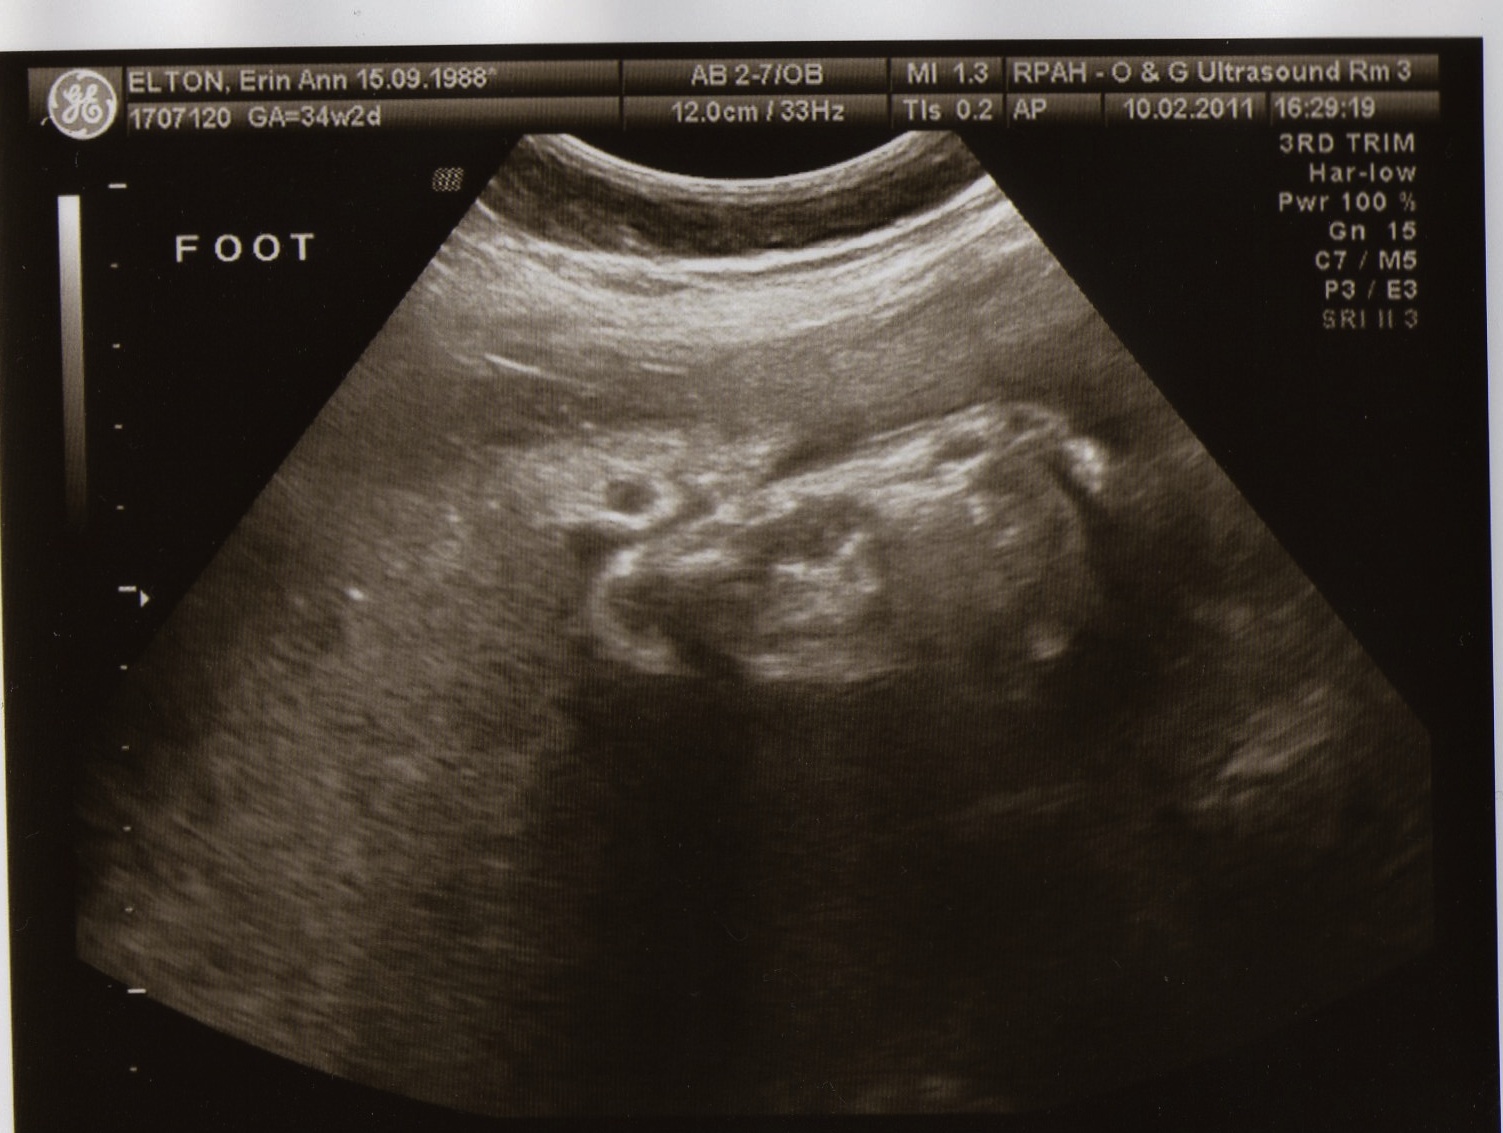

Big foot! Maybe she is a monkey?